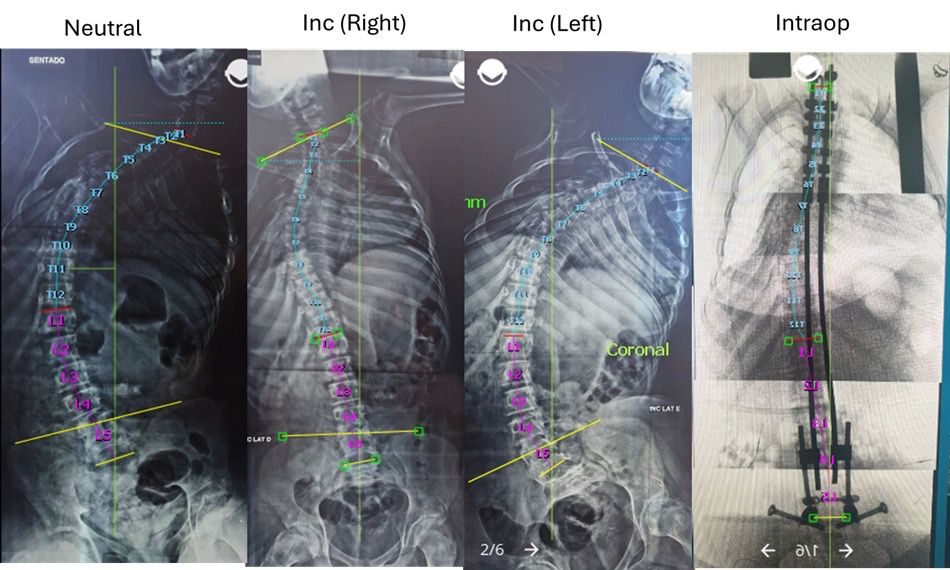

Apresentamos o caso de um paciente masculino, 20 anos, com escoliose neuromuscular grave e obliquidade pélvica marcada, associada a desalinhamento sagital global.

Os exames de imagem pré-operatórios mostraram uma curva escoliótica de alta magnitude, com baixa capacidade de compensação, o que resultava em dificuldades de posicionamento, higiene e mobilidade.

Durante o procedimento, a modelagem sequencial das hastes e as manobras graduais de redução possibilitaram a correção do plano coronal, o restabelecimento do alinhamento sagital e a horizontalização da pelve.

Os exames radiográficos pós-operatórios da técnica bipolar demonstraram uma melhora significativa do ângulo de Cobb, além da correção dos parâmetros sagitais e pélvicos.